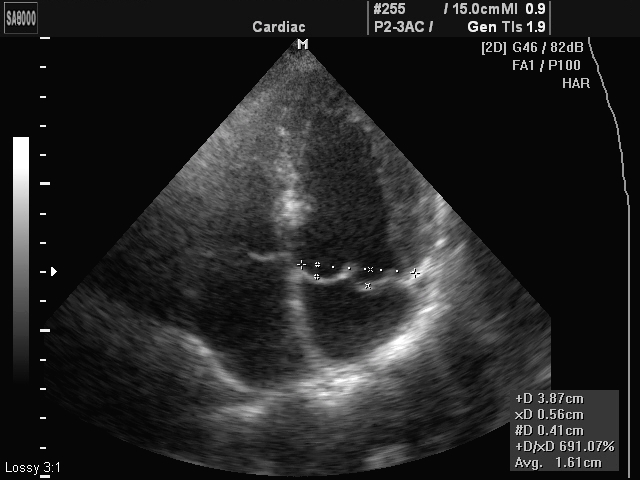

Если электрокардиография покажет только наличие нарушения, его стадию, то УЗИ сердца сможет дать более полное информирование, потому как позволит определить размеры створок, особенности их деформации, проще говоря, все патологические изменения, имеющие место в данном случае.